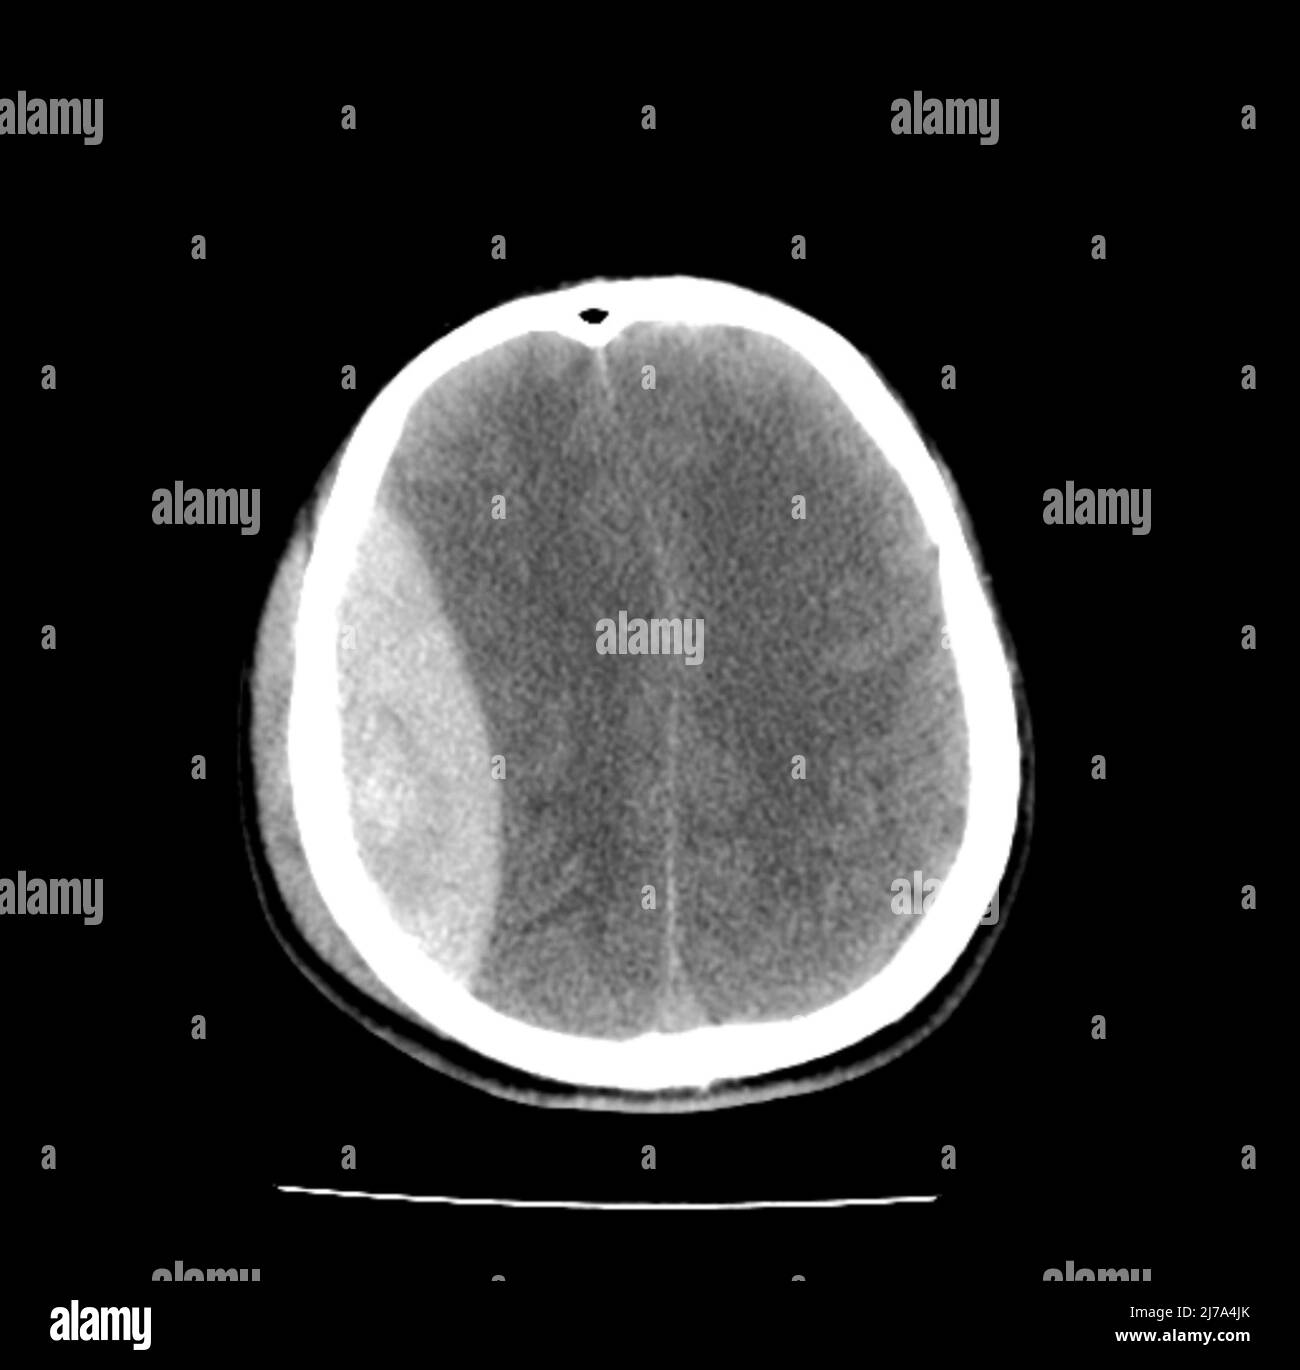

Concussion Brain Scan Photos and Premium High Res Pictures Getty Images Ct Scan For Concussion learn about different concussion tests that assess your brain function after a head injury. this means an imaging technology such as magnetic resonance imaging (mri) or computed tomography (ct) that can diagnose a severe traumatic brain injury (tbi), isn't a viable way to diagnose a concussion. a ct scan may be indicated when it is likely a. Ct Scan For Concussion.